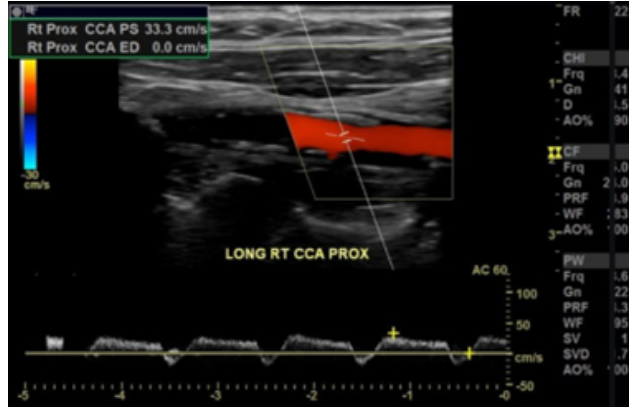

Observe a imagem a abaixo, extraída de um estudo da carótida comum direita.

Assinale a alternativa CORRETA.

Assinale a alternativa CORRETA.